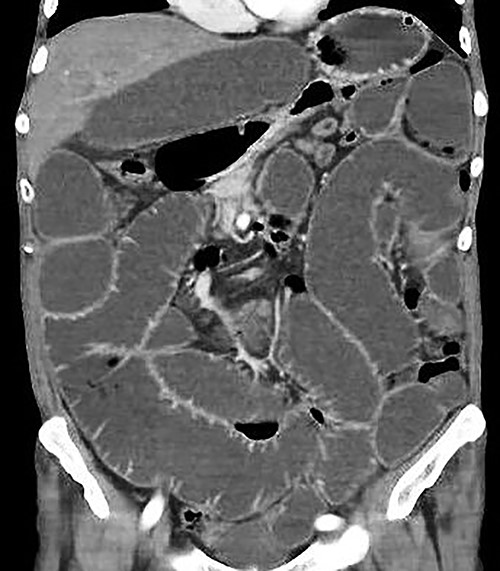

A supine and upright plain X-ray of the abdomen were obtained and showed dilated small bowel loops, mainly in the left upper abdomen, along with multiple air-fluid levels (Fig. 1). Computed tomography (CT) demonstrated significant air-fluid distention of the entire small bowel, up to the right flank and periumbilical region, where a change in caliber was observed (Fig. 2). The findings corresponded to small bowel obstruction (Fig. 3).

Abdominal and pelvic CT with intravenous contrast. Coronal image illustrating dilated fluid-filled loops of the small intestine consistent with high-grade mechanical obstruction.